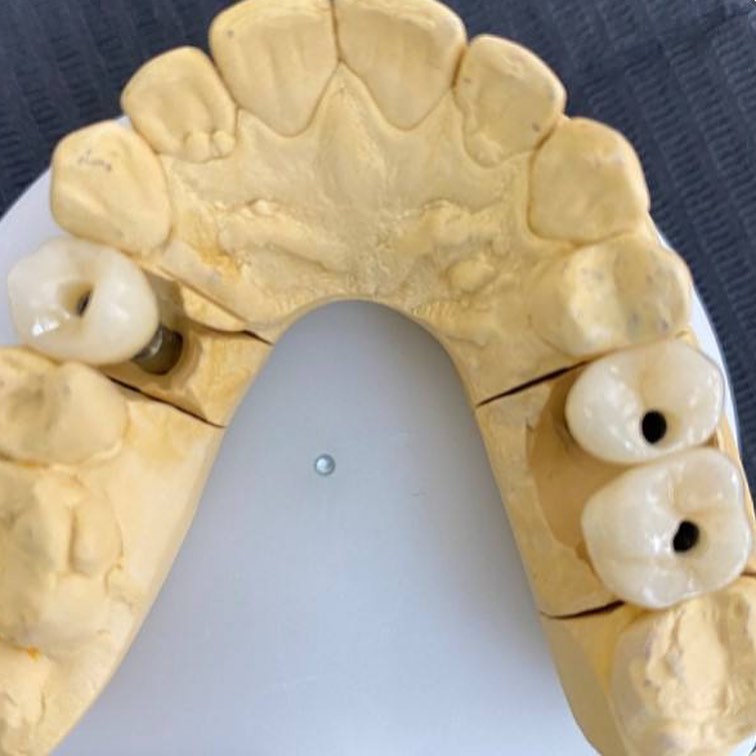

Клинический случай хирурга-имплантолога М. Подноса и врача-ортопеда М. Певзнера.

Винтовая фиксация, одномоментное формирование профиля прорезывания.

Винтовая фиксация.

Имплант Paltop Advanced 03.75мм, h10мм